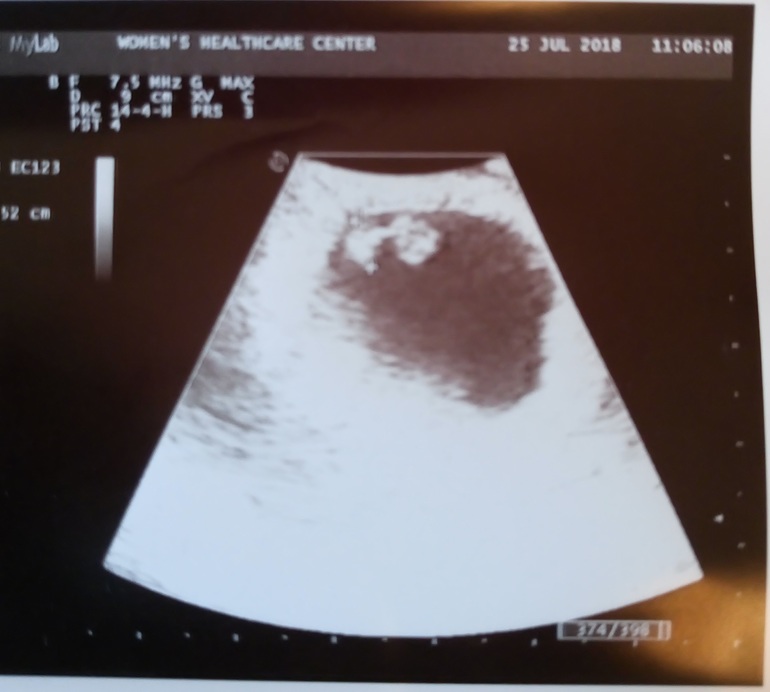

У нас получилось! Я беременна!Сегодня была на первом УЗИ. По моим подсчетам (овуляцию отслеживала тестами), сегодня 6+5 акушерский срок. Сердечко бьется, человек уже 5.2 мм. Хорошенький такой=)